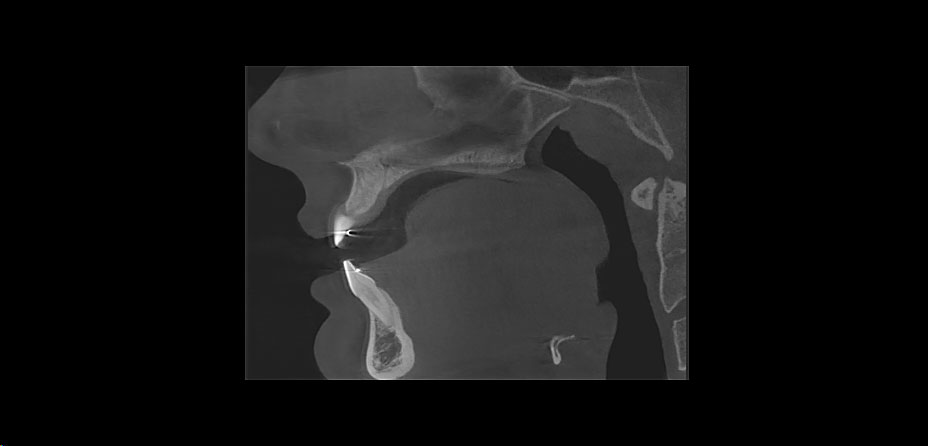

+ Bei chirurgischen Eingriffen, wie zum Beispiel Weisheitszahnentfernungen, können wir die Gefährdung benachbarter Strukturen wie Nerven und Nachbarzähne besser beurteilen und somit schützen

+ Auch bei der Beurteilung unklarer Beschwerden hilft die neue Technik. Auch kleinste Entzündungsherde und unauffällige, krankhafter Veränderungen können schnell entdeckt werden

+ Nach Unfallverletzungen lassen sich Brüche im Bereich des Kiefers und der Zähne zweifelsfrei diagnostizieren